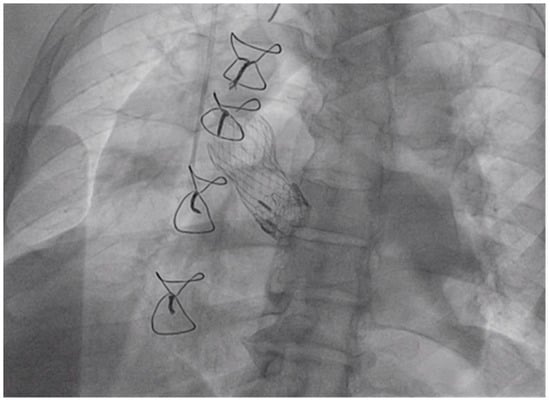

The procedure was performed under general anesthesia, using fluoroscopic and Transesophageal echocardiogram (TEE)guidance. Access for the TandemLife® was obtained in the left common femoral artery and right common femoral vein and both arteriotomy and veinotomy sites were “pre-closed” using two Perclose Proglide (Abbott Inc., Abbott Park, IL, USA) suture mediated vascular closure devices. A 22-French TandemLife® venous cannula in the right common femoral vein, and a 17-French TandemLife® arterial cannulae in the left common femoral artery was placed. The cannulae were then connected to the TandemLife® pump attached to an oxygenator. A cardiopulmonary bypass was initiated at a flow rate of 1.5 to 2 L per minute. Next, a 5 French balloon-tipped transvenous pacer was placed via a 7 French sheath in the left common femoral vein. The transvenous pacer was placed at the apex of the right ventricle, and threshold testing was performed confirming excellent position of pacer and capture. The right common femoral artery was then accessed and “pre-closed” using two Perclose Proglide suture mediated closure devices. A 14 French dry Gore Sheath (Gore Inc., Newark, Delaware, USA) was placed in the right common femoral artery through which a 6 French Judkins Right 4 (JR4) catheter and stiff angled Glidewire (Terumo, Somerset, NJ, USA) was used to cross the aortic valve. The JR4 was exchanged for a 6 French pigtail catheter, through which an Amplatz Super Stiff wire (Boston Scientific, Boston, MA, USA) was advanced into the apex of the left ventricle. The 26 mm Medtronic CoreValve Evolut-R was prepped and loaded onto the back table, if needed. Over the Amplatz Super Stiff wire, a 22 mm True balloon (Bard Inc., Tempe, AZ, USA) was placed in the aortic valve position. Rapid right ventricular pacing was initiated at 180 beats per minute, and the True balloon was inflated up to 12 atmospheres as shown in Figure 2, at which time the Carpentier–Edwards Perimount surgical bioprosthetic valve was fractured.

Figure 2.

Left Anterior Oblique (LAO) Caudal View: True balloon fracturing the surgical bioprosthetic valve. The transvenous pacemaker in place.